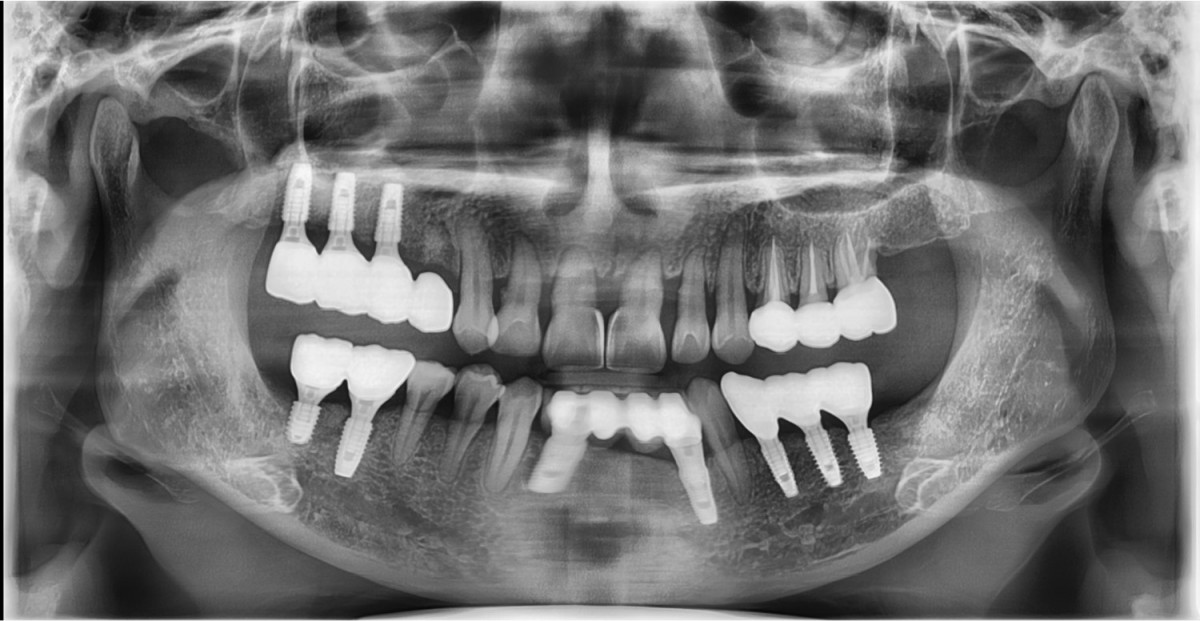

▲Implant placement GBR

▲GBR(Xenograft).